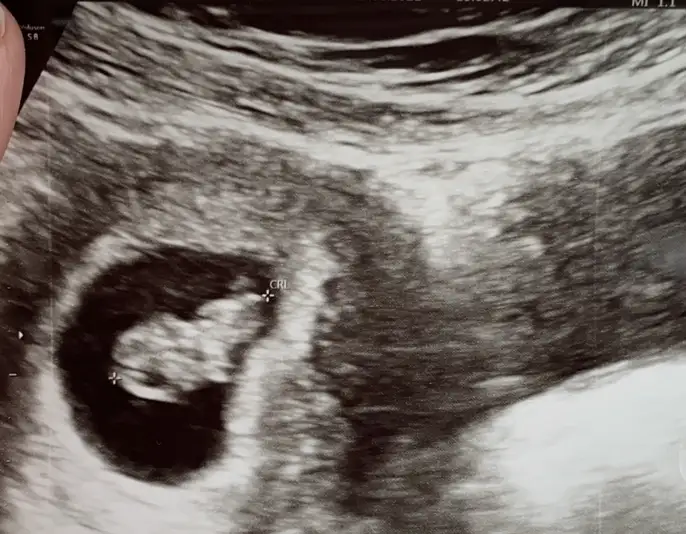

Selamlar herkese 😊 sabah doktora gittim baya büyümüş 🙈👶🏼 bes alti tup kan alindi hem kan testi hem ikili test icin bir de idrar tahlili istedi doktor. İnşallah güzel çıkacak sonuçlar 🙏

T tulperde rica etsem tahmin alabilir miyim cok arada kaldım 🙈 doktor bisey demedi

Pek tatlı biseye benziyor😍 sağlıcakla kucagina al ins